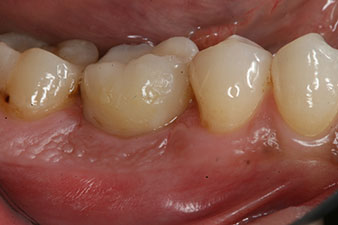

Las figuras finales muestran la corona de composite monolítica atornillada in situ y la radiografía de control (figuras 9 y 10) (6).